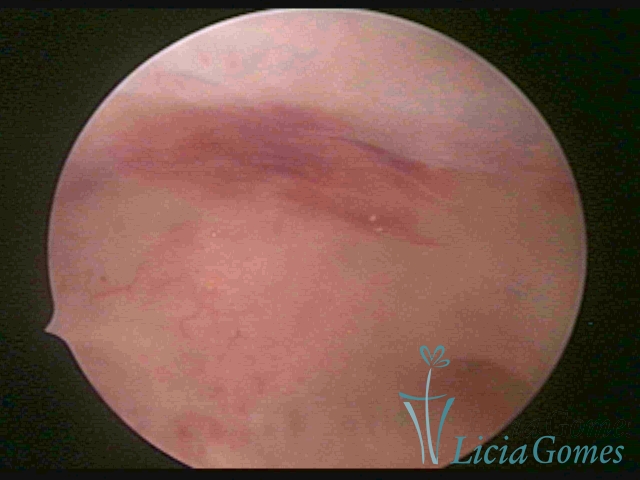

ACUTE ENDOMETRITIS

In video hysteroscopy, we observe the endometrium bleeding, its endometrial surface is speckled, presenting a “creamy” aspect and a whitish color with a brightness enhanced by the fibrin accumulated. Bluish or rough areas, which may correspond to cystic necrosis. The presence of adhering mucus or pyometra may occur.